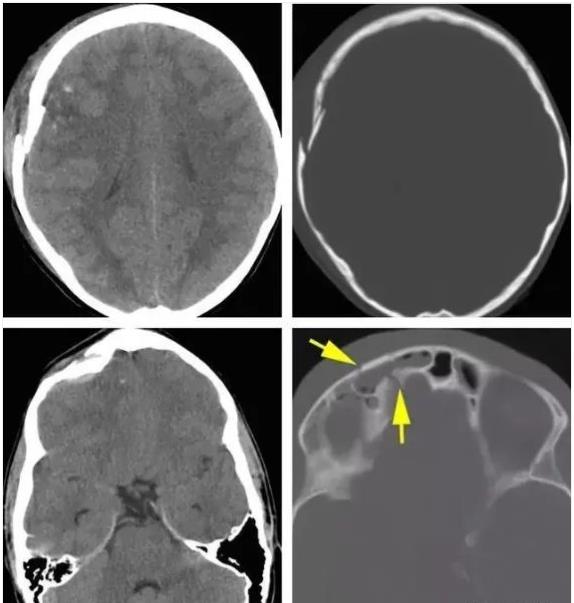

影像学表现:

根据形态的不同,可出现凹陷、线状、粉碎性和空洞性等,外伤后颅内气体可提示颅骨骨折。